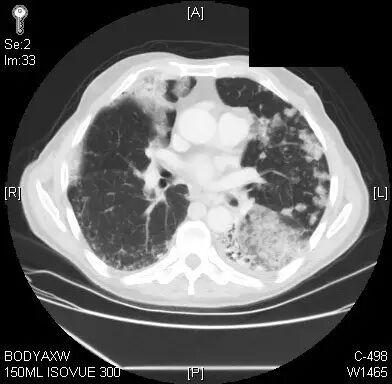

患者今年69岁,是退休纺织工人,具有未充分控制的高血压和抑郁症。在过去6个月内,他出现咳嗽,有清痰,活动时呼吸浅短。影像学表现与多灶性肺炎一致。患者接受了多个疗程的抗生素以及强的松治疗,但症状未得到改善。患者的初级护理医生进行随访,获得了胸部计算机断层扫描(CT)扫描,结果显示双侧肺实变影加重(图1)。

图1.胸部CT